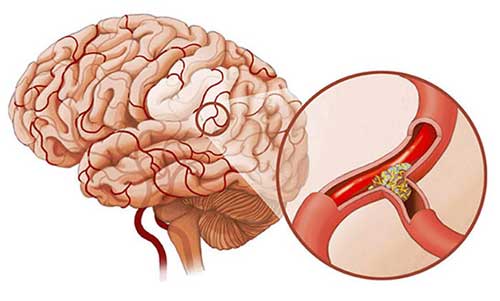

Закупорка артерий головного мозга чаще всего возникает из-за образования бляшек.

Атеросклероз сонных артерий приводит к образованию тромба, состоящего из холестерина. Постоянное накопление бляшек на стенках сосудов вызывает сужение их просвета или полную блокировку.

Хрупкость таких тромбов приводит к тому, что от них отрываются эмболы — небольшие частицы, которые с кровотоком перемещаются по сосудам головного мозга. Это создает риск развития ишемического инсульта.

Образование тромба в артерии приводит к основному симптоматическому проявлению — нарушению кровоснабжения, известному как ишемия. Поскольку установление точной причины нарушения кровотока представляет собой сложную задачу, различение таких состояний, как ишемический инсульт и тромбоз артерий головного мозга, остается не совсем ясным.

- атеросклероз;